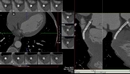

Anjiyo, kalp damarlarının görüntülenmesi için yapılan invaziv bir tanı yöntemidir. Bu işlem, genellikle koroner arter hastalığını değerlendirmek ve tedavi seçeneklerini belirlemek amacıyla gerçekleştirilir. Anjiyo süresi, birçok faktöre bağlı olarak değişiklik gösterebilir. Bu makalede, anjiyo işleminin süresi, aşamaları ve bu süreyi etkileyen faktörler ele alınacaktır. Anjiyo İşleminin AşamalarıAnjiyo işlemi, genel olarak aşağıdaki aşamalardan oluşur: